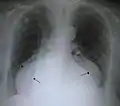

A large hiatal hernia on chest X-ray marked by open arrows in contrast to the heart borders marked by closed arrows

This hiatal hernia is mainly identified by an air-fluid level (labeled with arrows).